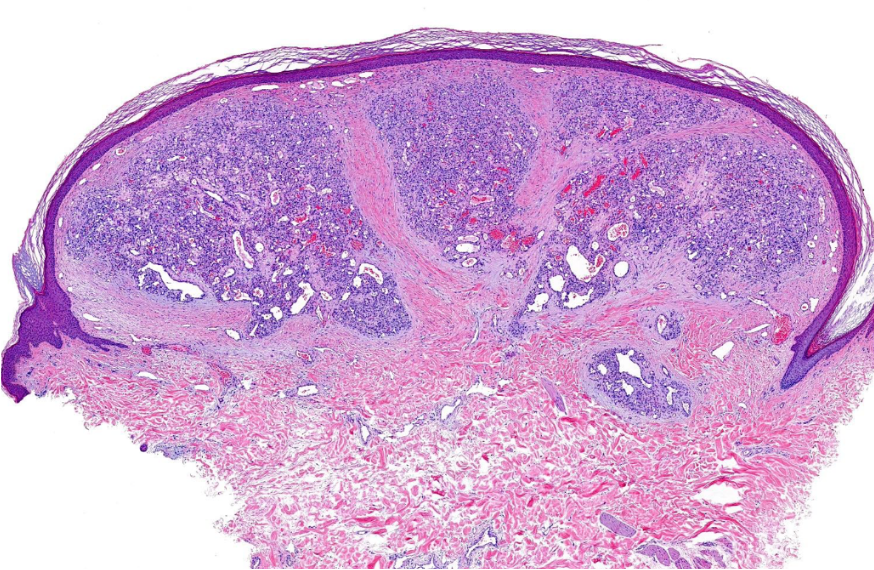

Aufgrund des raschen Größenwachstums mit möglicher Alteration des Nagelwachstums, zur sicheren Abklärung der Dignität und insbesondere auch auf Wunsch der Patientin, erfolgte die handchirurgische Entfernung der Läsion. In der Histologie bestätigte sich die Arbeitsdiagnose eines sogenannten Granuluma pyogenicums bzw. ätiologisch exakt, eines eruptiven Hämamgioms (Abb. 2).

Abb. 2. Typische Histologie eines Granuloma pyogenicum mit multiplen lobulären Kapillarkonvoluten in der Dermis mit bindegewebigen Septen und möglicher Erosion der darüberliegenden Epidermis mit neutrophiler und lymphozytärer Infiltration (a,b). Typisch ist die seitliche epitheliale Collerette (Kragenbildung).